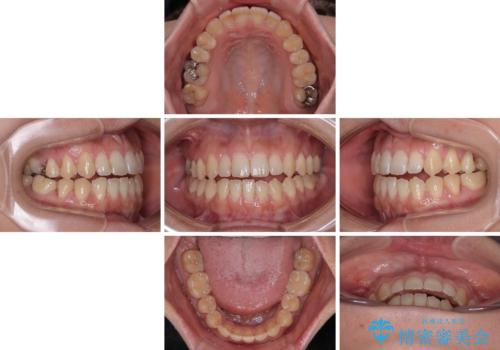

- 極端な開咬を気にして来院された患者様です。

開咬の方の特徴として、幼少期の指しゃぶりの癖や、強い舌の突出癖が挙げられます。

こちらの患者様も強い舌の突出癖が認められたため、矯正治療を行うにあたり、舌のトレーニングをしっかりと行っていただくように指示をいたしました。

開咬はインビザラインが得意とする歯列不正であるため、舌のトレーニングを行いながら、インビザラインにて矯正治療を行うこととしました。

担当医としては、もっと上下の前歯を接触させるところまで治療を進めたいという思いがありますが、今まで咀嚼できなかったものが食べられるようになったということで、この状態で治療終了となりました。